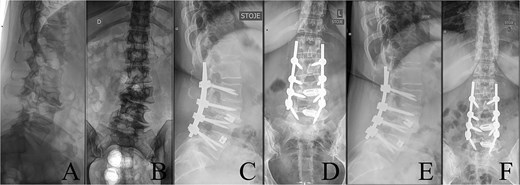

Last preoperative X-ray, lateral (A) and anteroposterior view (B). After 10 weeks of follow-up; lateral (C) and anteroposterior view (D). After 1 year of follow-up; lateral (E) and anteroposterior view (F).

A 43-year-old female with a history of a previous isolated right-sided L3 foraminotomy at an external facility (this intervention temporarily alleviated her leg pain but exacerbated her back pain) was referred to our institution due to chronic back pain, right-sided leg pain without neurological dysfunction, and a forward-leaning posture, which was correctable with verbal cues. The back pain, in the absence of neurological deficits, began 13 years prior, at which time she was diagnosed with adult congenital scoliosis caused by L3 hemivertebrae (Figs 1 and 2). Imaging confirmed a L3 hemivertebra resulting in a 24° Cobb angle of congenital scoliosis (Fig. 1), without associated cord abnormalities on MRI.

The postoperative course was uneventful, with no evidence of neurological dysfunction. The patient commenced physiotherapy on the first postoperative day. At the initial follow-up, 10 weeks post-surgery, she was ambulating unassisted with reduced back and leg pain, without neurological impairment but with a persistent forward-leaning posture that remained correctable with verbal cues. At the final follow-up, one year after surgery, she reported resurgence of forward-leaning posture after longer walks, and referred to a tertiary rehabilitation institution. Imaging demonstrated L2–L5 fusion with no signs of instability or residual deformity (Fig. 1).